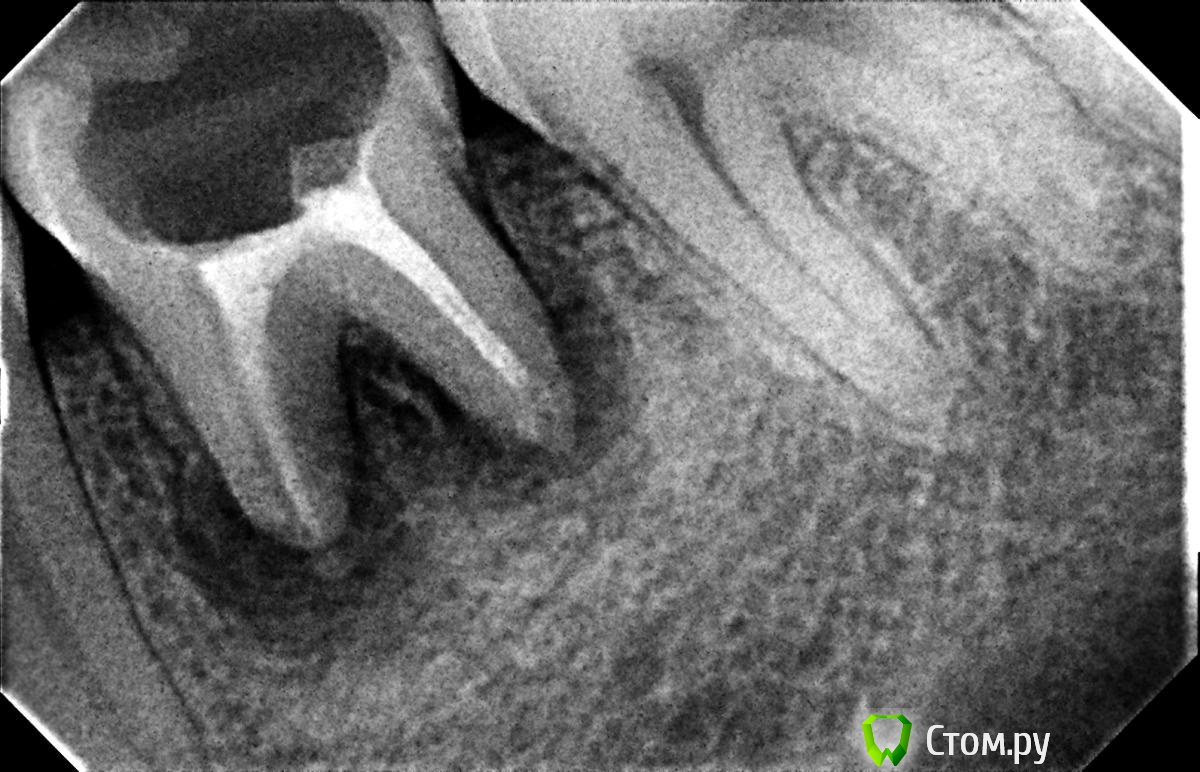

Hans85 Опубликовано 10 января, 2014 Автор Поделиться Опубликовано 10 января, 2014 (изменено) .Новый кейс-совсем свежий пока без долгосрочного результата.Пациентка попала случайно удаляла зуб 28 и хирург сделал ОПТГ,где стали видны обширные периапикальные процессы в области 37 47.Побывав у меня на консультации и услышав план лечения и стоимость,пациентка решила видимо полечить подешевле.,побывав на консультациях в нескольких клиниках и в итоге даже попала к главному стоматологу нашей области. Все ей сказали что удаление онли. Вернулась,-засада была в том что план я писал исходя из ОТПГ не сделав прицел(виноват),сделав прицел понимаю что все сложнее чем я думал-ну что же тем интереснее.Переписав план лечения и подняв ценник на 40%(пациентке не оставалась выбора),начали лечение.1-посещение-ревизия пломбы.понимаю что кто то до меня с маниакальным упорством пытался запломбировать мезиальный язычный канал каналонаполнителями. Убрал два фрагмента из верхней трети мезиального язычного.2-посещение еще фрагмент из мез язычного плюс немного с дистальными поработал(их оказалось два сплит в верхней трети)3-визит обошел фрагмент в мезиальном щечном и доработал остальные каналы.4-визит -паковка.На предпоследнем снимке видны поры-допаковал(просто на финальном не очень видно) Изменено 10 января, 2014 пользователем Hans85 Ссылка на комментарий